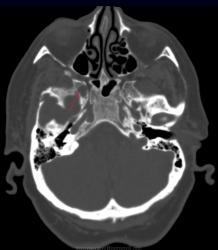

Метастазы в костях основания черепа.

Женщина средних лет с клиникой невралгии тройничного нерва справа. На КТ были выявлены округлые очаги деструкции в костях основания черепа (средней черепной ямки).

Наблюдение Nela.